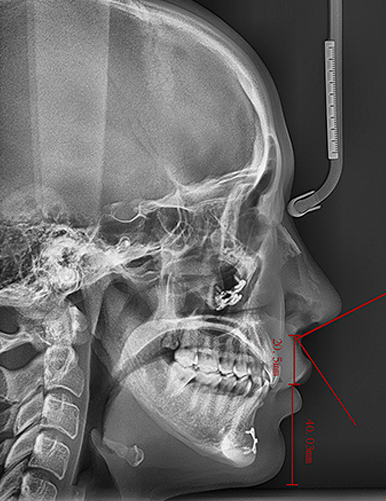

정승일 대표원장의 노하우로 개인의 골격·근육 움직임·입술 형태를 정밀 분석하여 이상적인 비순각(Nasolabial Angle)과 옆라인을 구현합니다. 단순 교정이 아닌, 얼굴 전체의 조화로운 재설계입니다.

개개인의 골격·근육 움직임·입술 형태를 분석해

가장 이상적인 비순각(Nasolabial Angle) 과 옆라인을 완성합니다.